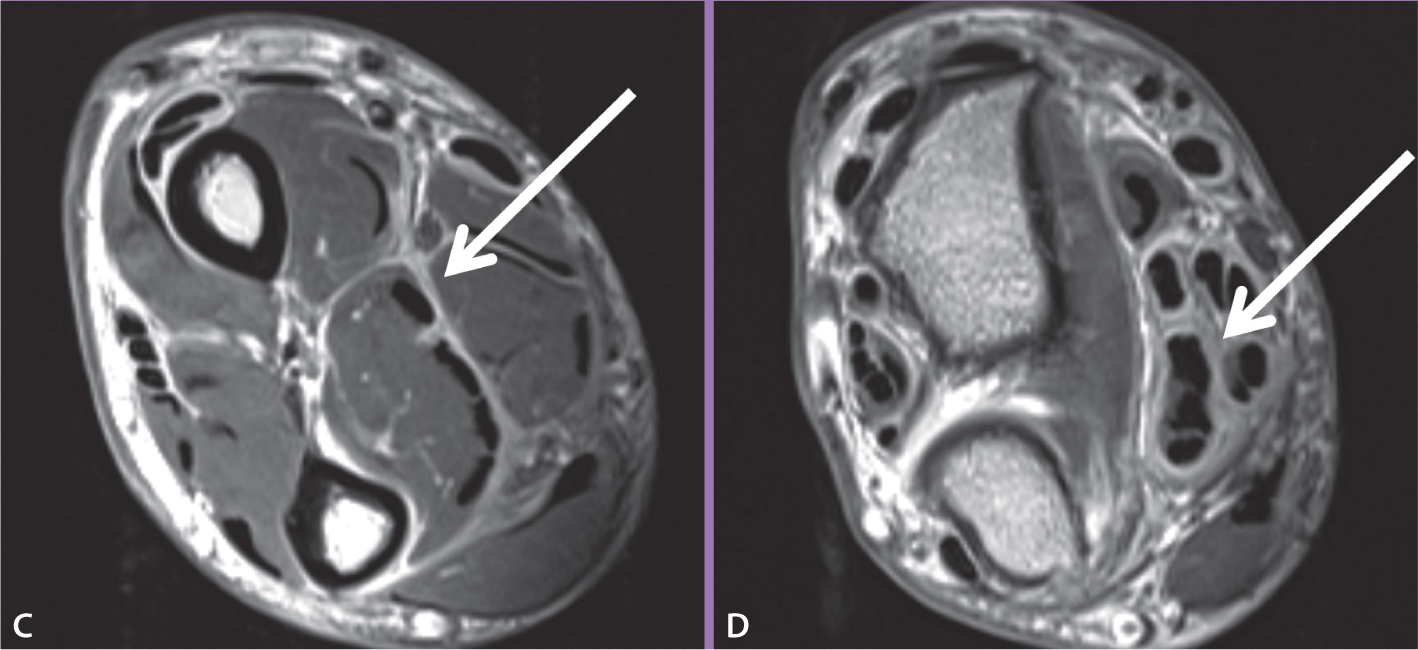

Verdickte Muskelfaszien (links, Pfeil) und Sehnenscheiden (rechts, Pfeil).

Ein MRT seines rechten Vorderarms zeigte erheblich verdickte Muskelfaszien (Abb. C) und Sehnenscheiden (Abb. D) mit einer jeweils starken Kontrastmittelanreicherung. Die Entnahme einer tiefen Gewebeprobe ergab die histologische Diagnose einer eosinophilen Fasziitis mit Fibrinexsudaten, Fibrosen und lymphoplasmazellulären Infiltrationen der Faszien sowie einzelnen eosinophilen Granulozyten. Der Patient erhielt eine Behandlung mit oral verabreichten Kortikosteroiden mit einer initialen Dosis von 70 mg/d, die dann über eine Zeitraum von zwei Monaten schrittweise auf 10 mg/d reduziert wurde. Die klinischen Symptome besserten sich hierdurch maßgeblich.